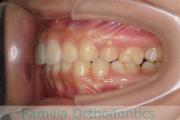

No.20V-496

- 叢生

- 15歳

- 女性

- 上:

- 84|58

- 下:

- 8558

- FEA

- 80万円

全体的なでこぼこを治したいということで来院されました。上顎は右は4,左と下顎両側は5番を抜歯して、マルチブラケット法にて治療を行いました。2年強、25回程度の通院をしていただきました。

非常に強いでこぼこですので、後戻りのリスクは高めであると思われます。